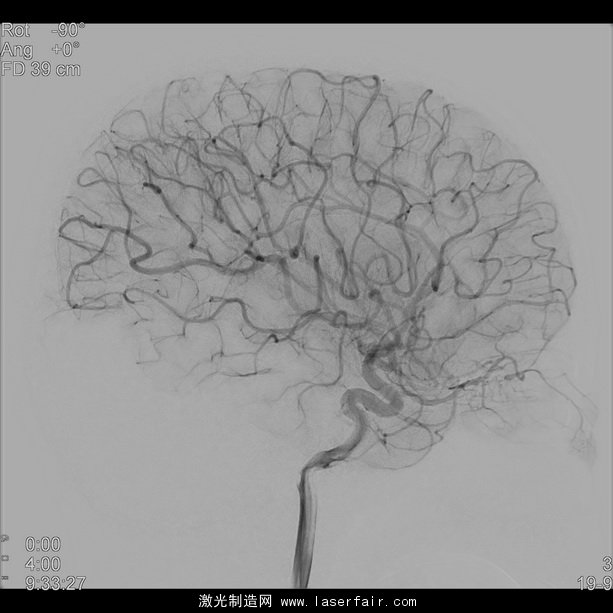

為應(yīng)對(duì)這些困難,飛利浦的 NeuroSuite 包含一個(gè)雙面介入式 X 射線系統(tǒng),并獨(dú)家整合了兩款新探測(cè)器:飛利浦前額 FD20探測(cè)器提供實(shí)時(shí)的2D 和3D 影像以實(shí)現(xiàn)實(shí)時(shí)導(dǎo)航和即時(shí)療法反饋;小型側(cè)面 FD15探測(cè)器可放置于遠(yuǎn)離雙肩和非??拷^部的部位。這樣的更短距離和獨(dú)特的探測(cè)器結(jié)合,能以更少的 X 射線劑量提供清晰的全腦影像,以及對(duì)神經(jīng)與脊椎介入進(jìn)行了優(yōu)化的3D 影像。

卡羅林斯卡大學(xué)醫(yī)院神經(jīng)放射科副主任醫(yī)師、神經(jīng)造影和立體定向主管 Michael Soderman 醫(yī)師說(shuō):“血管造影術(shù)系統(tǒng)在介入式神經(jīng)放射科的表現(xiàn)對(duì)患者的安全極為重要。飛利浦的最新創(chuàng)新是在額狀面有著20英寸新探測(cè)器的 NeuroSuite,能提供極好的3D 影像和足夠大的脊椎影像。側(cè)面則有15英寸的新探測(cè)器能提供完整的大腦血管影像,可減少碰撞危險(xiǎn)并促進(jìn)投影自由。”

NeuroSuite 的中心是將放射劑量減少了73%且不犧牲影像品質(zhì)[2],[3]的飛利浦 AlluraClarity,以及在血管背景和血管組織直至穿支血管中可視化顱內(nèi)設(shè)備[1]的VasoCT。